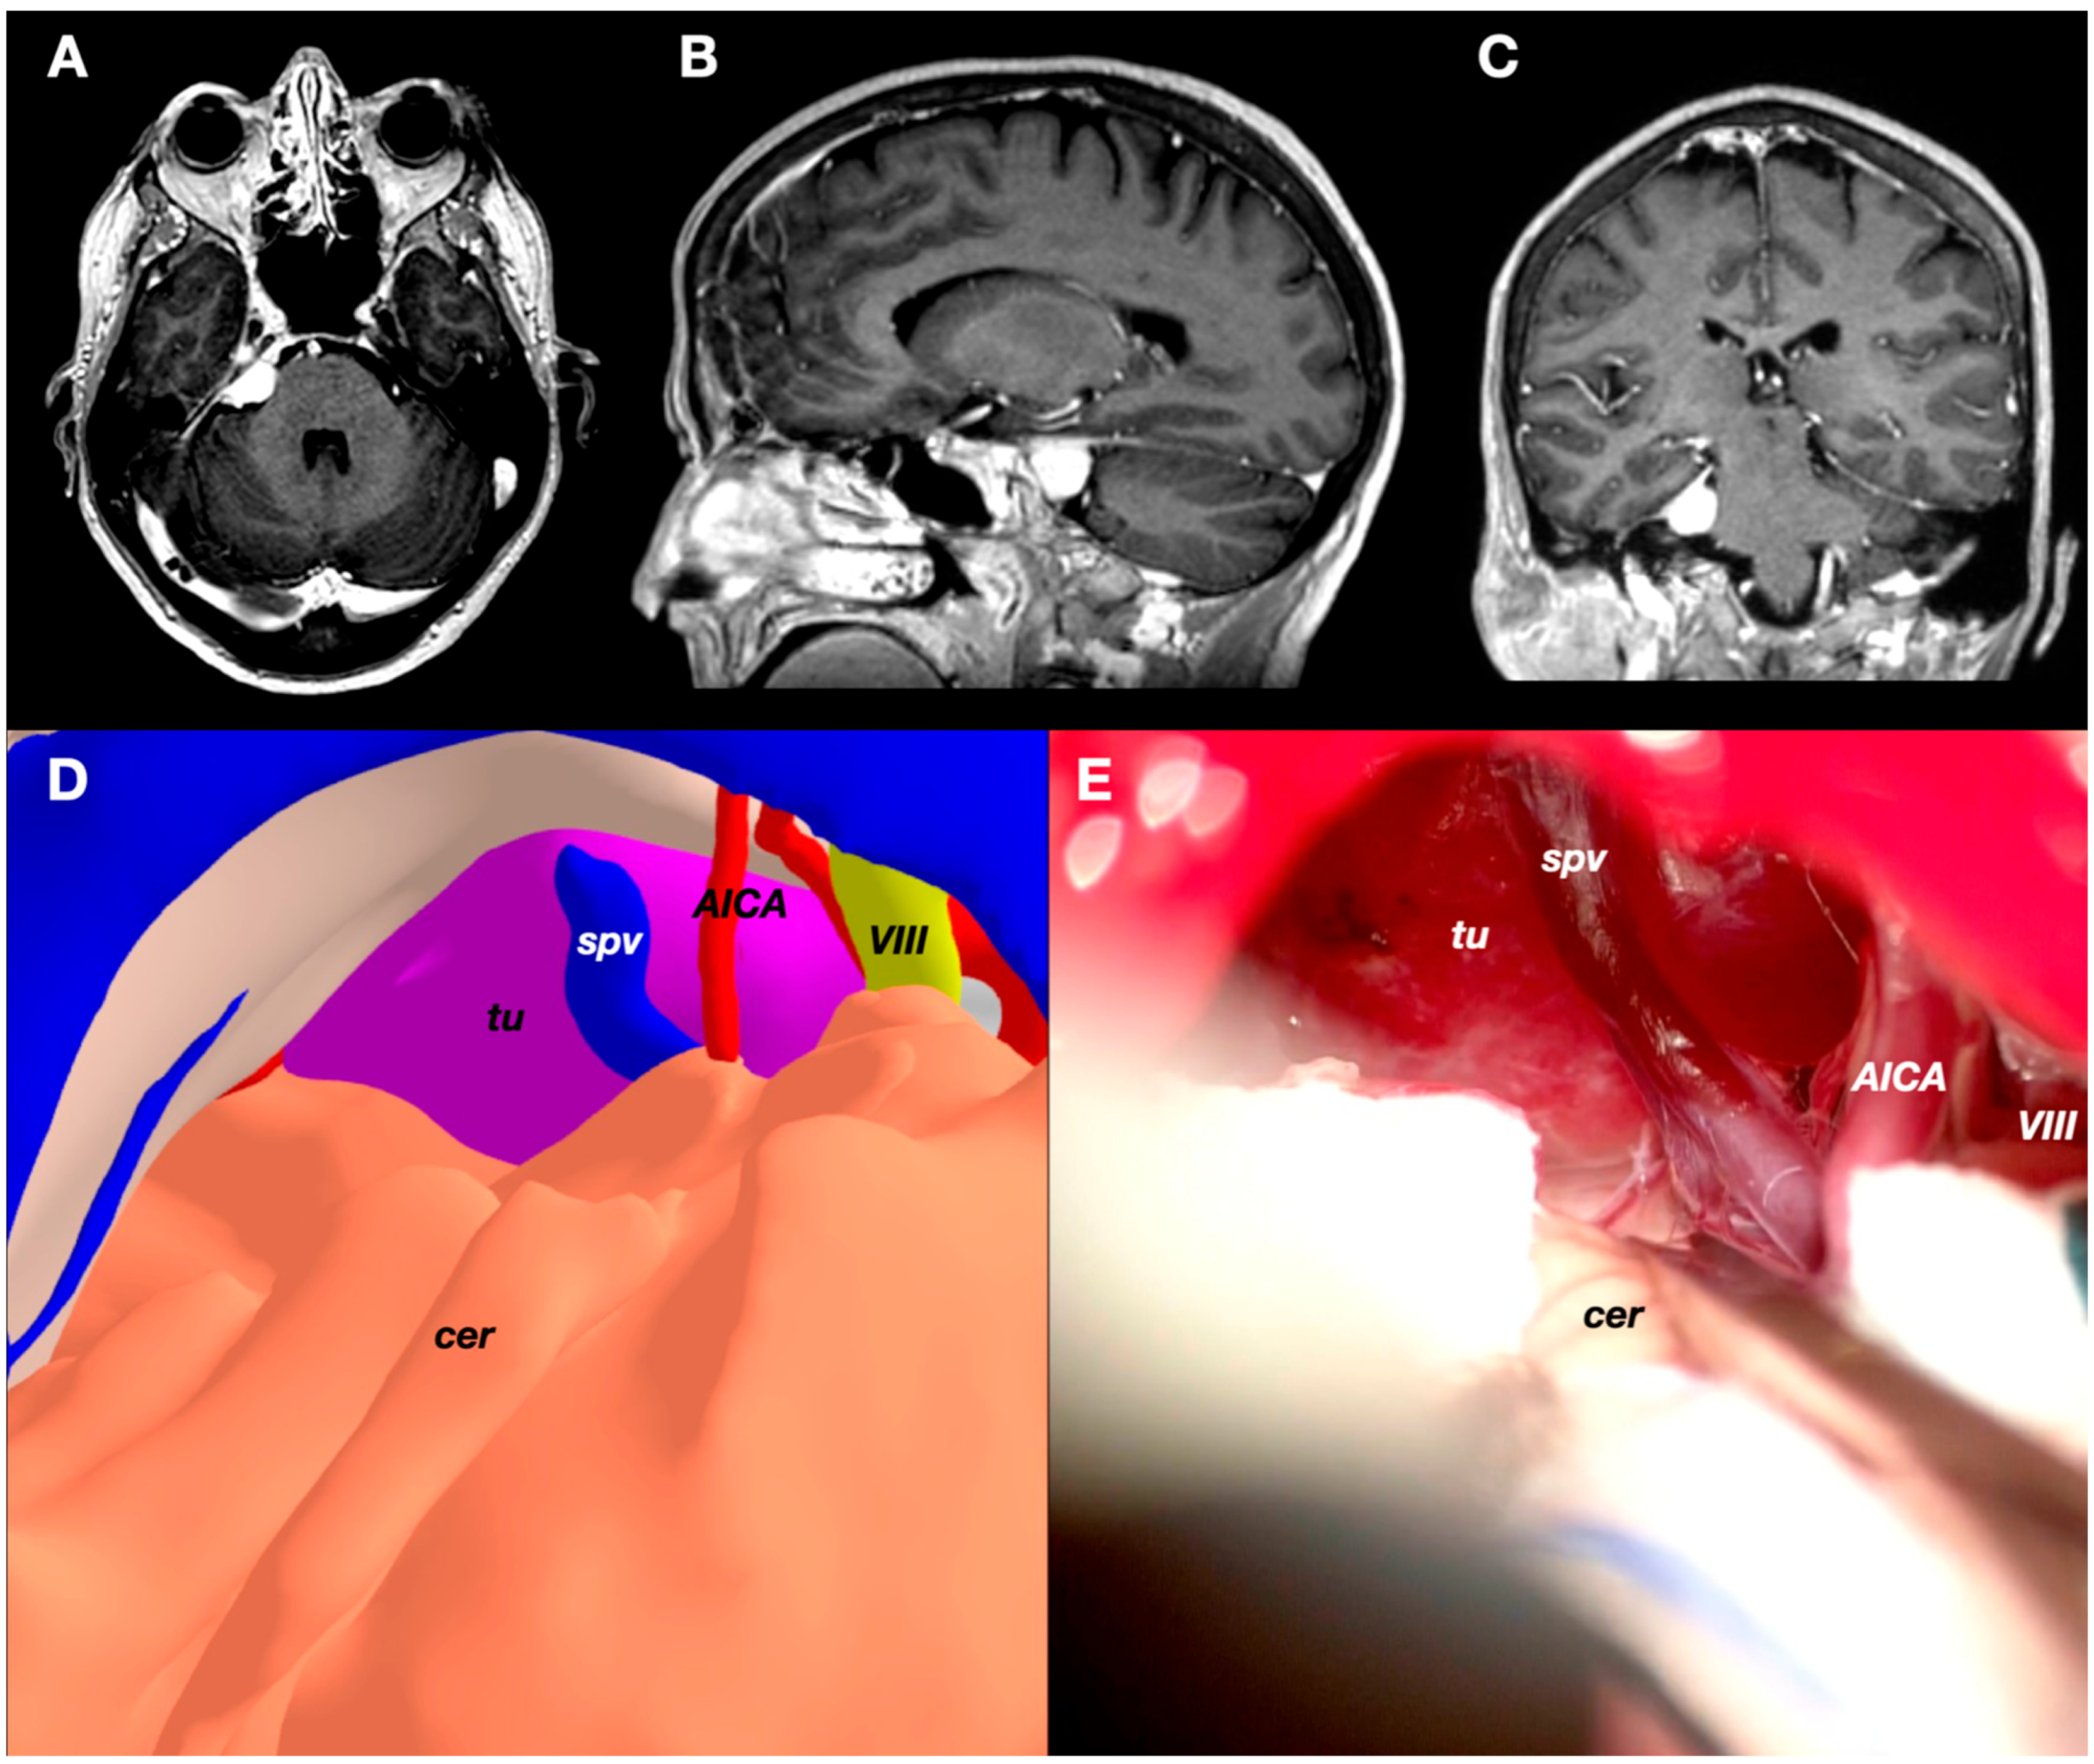

3.4. Case 4: Foramen Magnum Meningioma